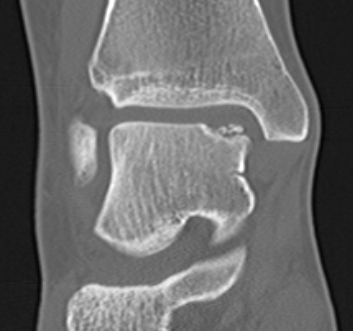

CT

Stage III

Stage IV displaced fragment with osteochondral defect